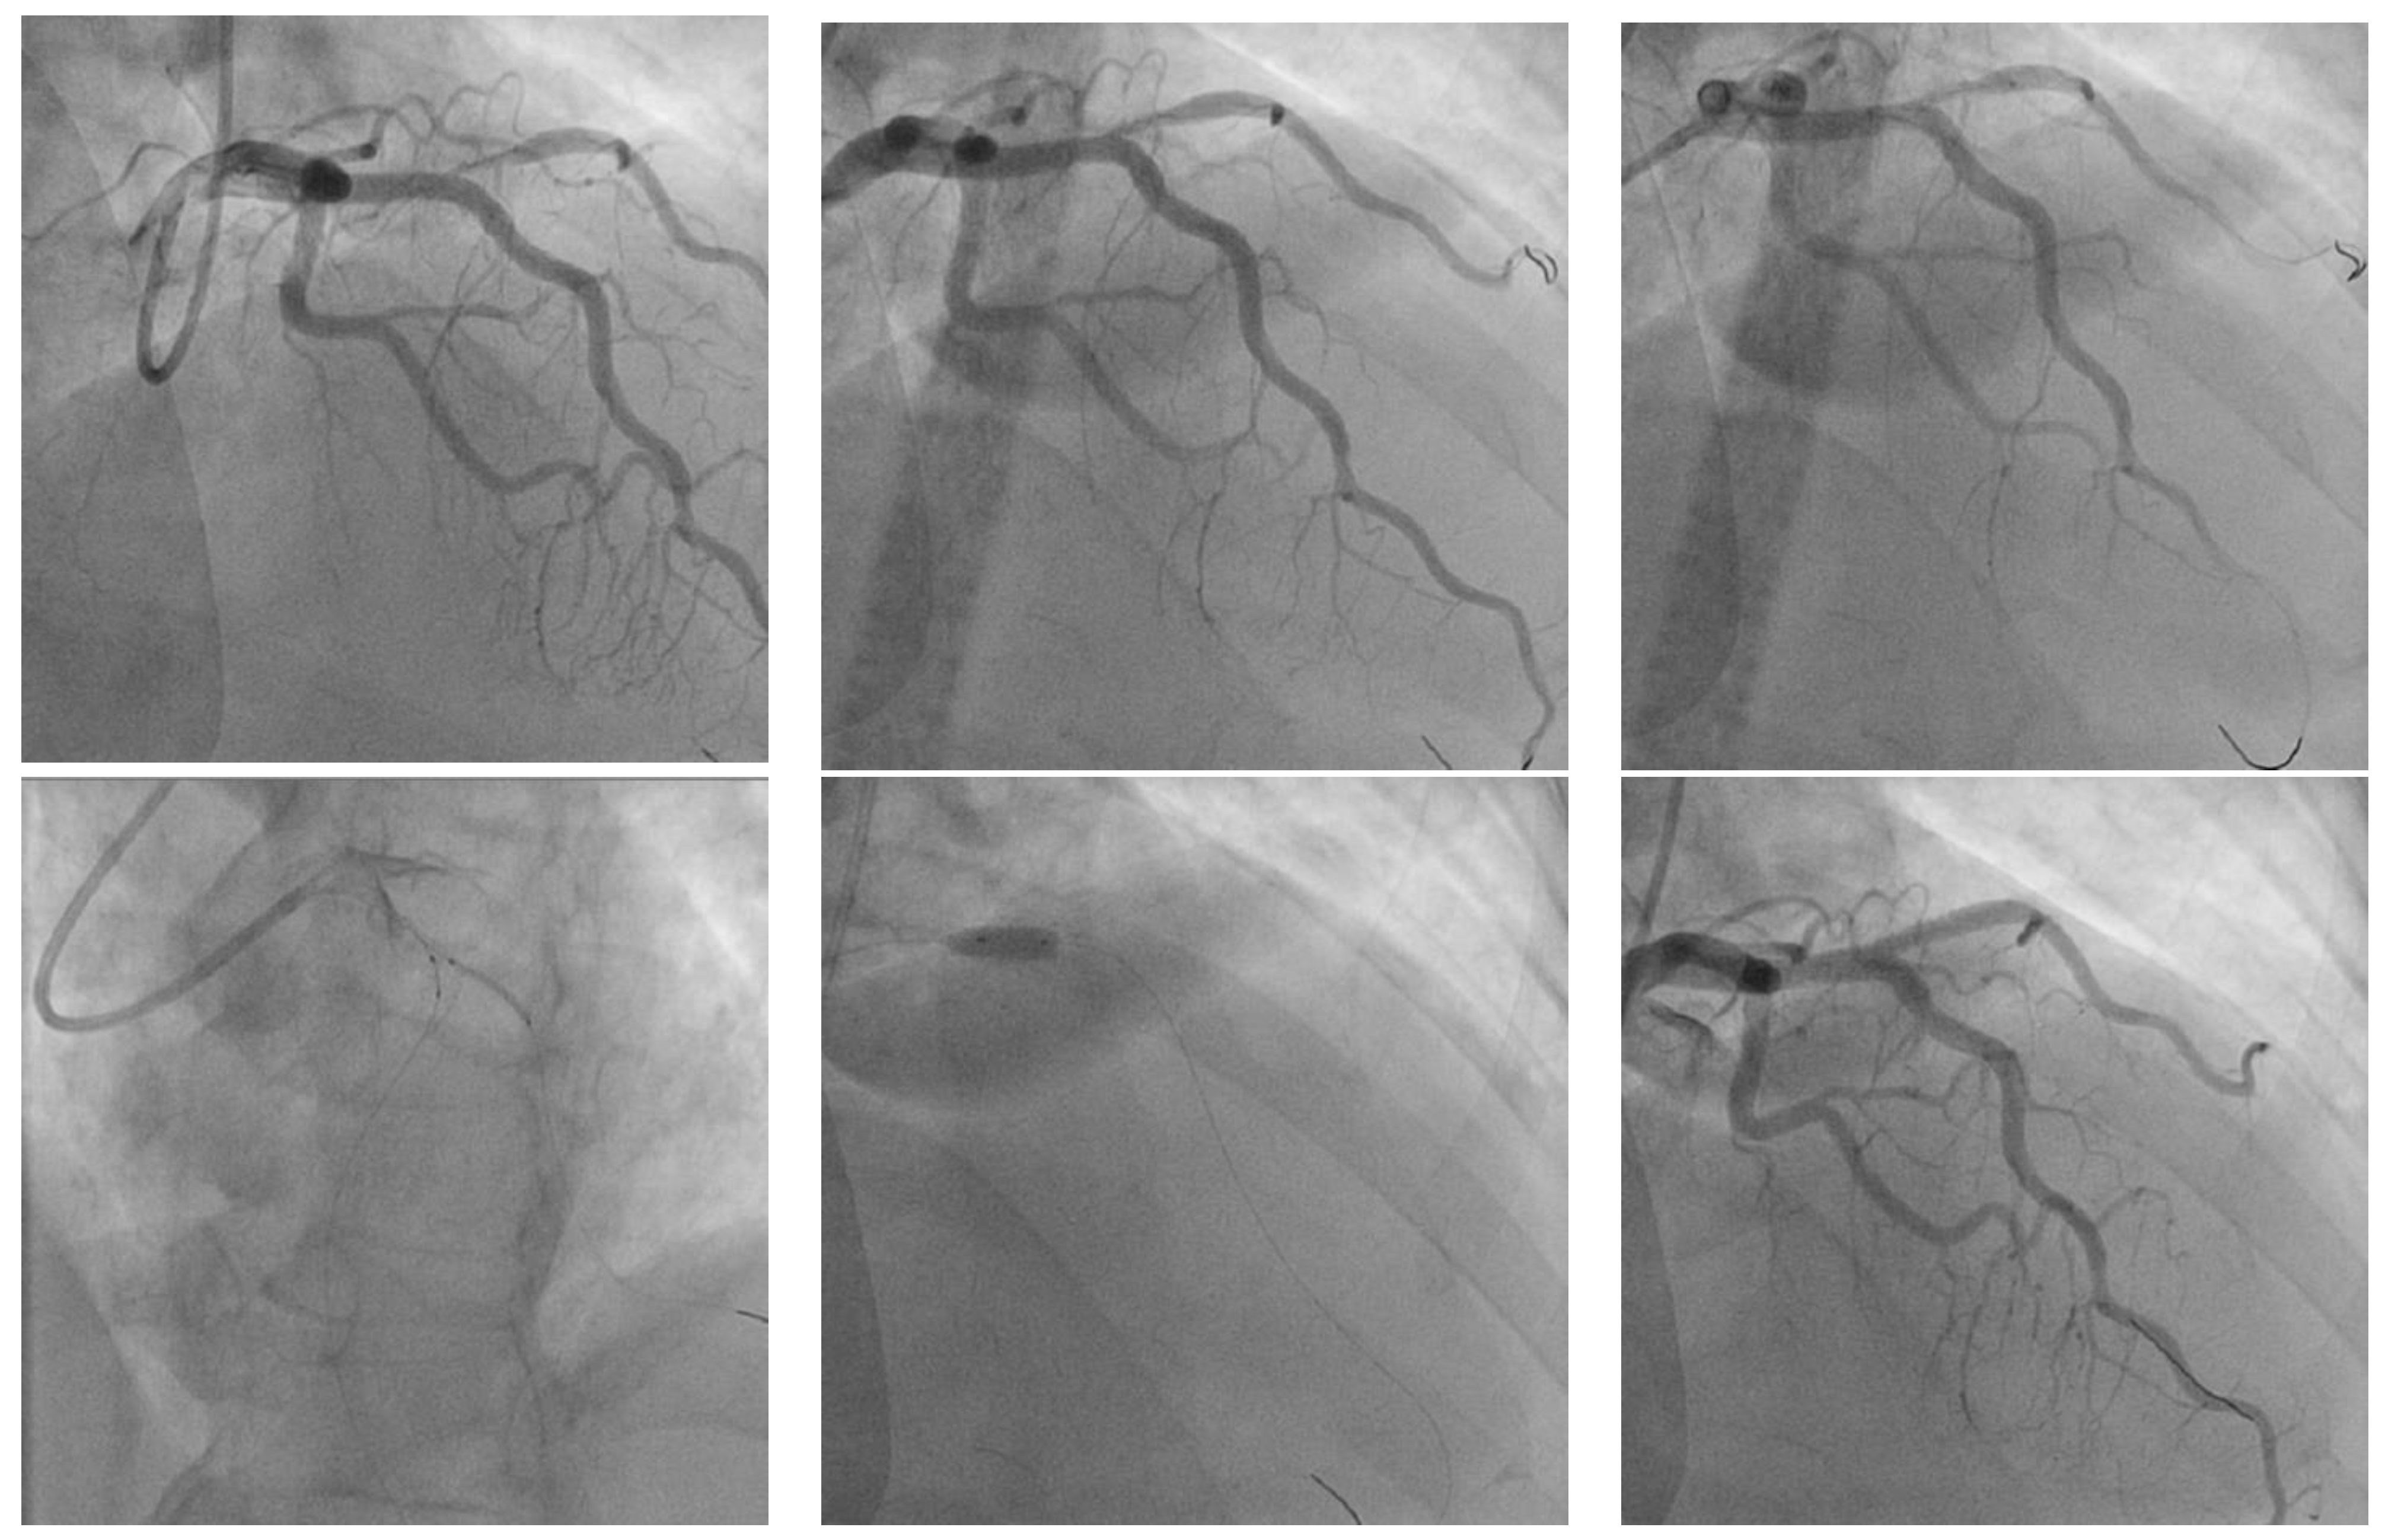

T and Small Protrusion (TAP) Technique in Bifurcations: Coronary Artery Disease in Acute Myocardial Infarction Patients after COVID-19 Pneumonia

2. Case Presentation